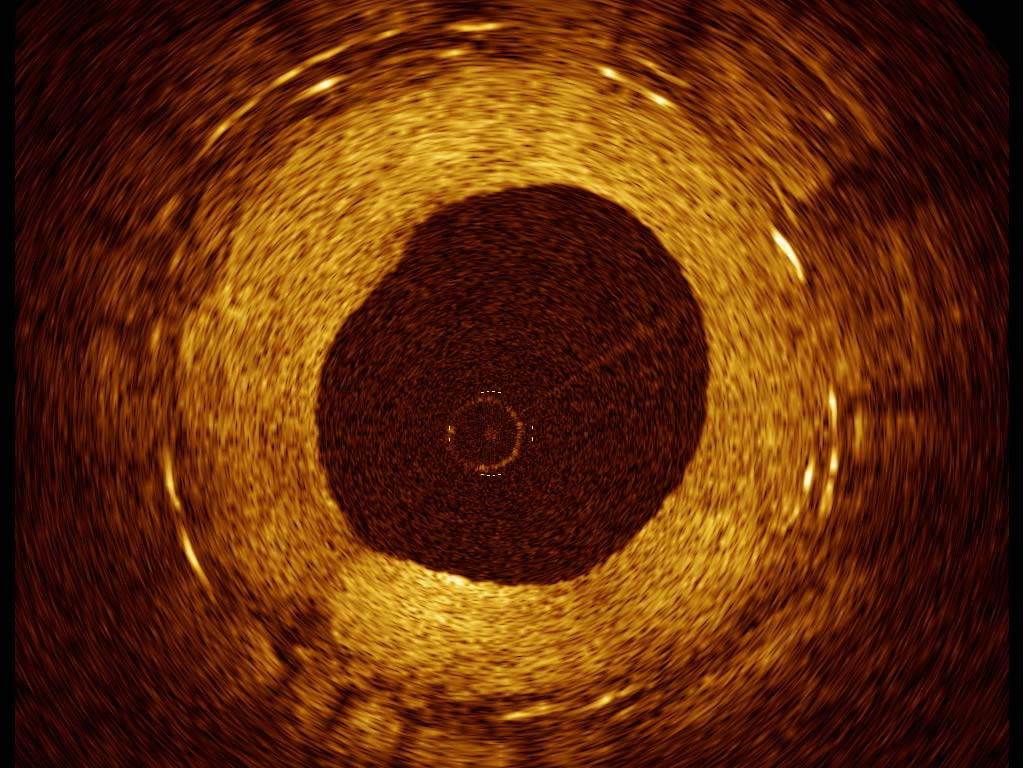

Groundbreakers in OCT, CMR and Cardiac CT Technology

We are the global leader in optical coherence tomography (OCT). OCT is a breakthrough intravascular imaging technology that allows clinicians to readily see and measure important blood vessel characteristics that were previously invisible or difficult to observe with older intracoronary imaging modalities.